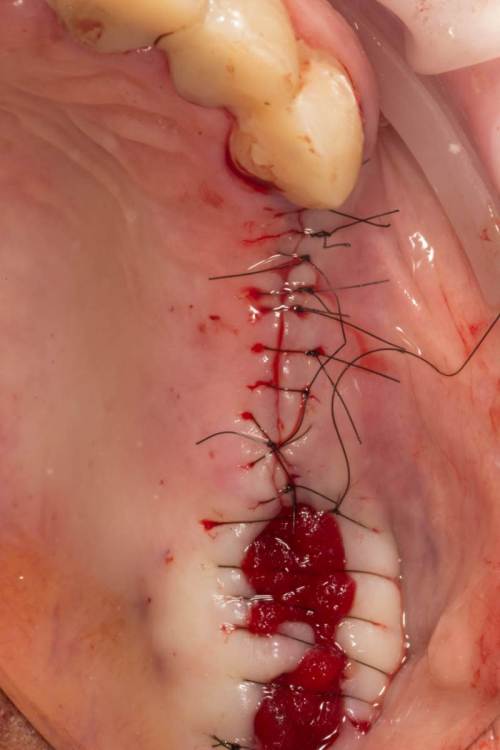

Женька Опубликовано 24 июля, 2023 Поделиться Опубликовано 24 июля, 2023 Тема ради одной фотки конечно, но всё-таки вопрос есть. Говорят МСТ профайлер не задевает стенки имплантата. Кмк, всё-таки задевает. Или всё-таки кажется? По кейсу: 2 имплантата, оба по шаблону. Черт дёрнул пройти глубже чем планировал в 1.6, фрезой перфо не создал, но кортикалку в ноль убрал. И при отслойке всё-таки порвал немного. Тампонировал губками, пробы отрицательные. Вроде нигде не перемудрил в этот раз, @АнтонТЛТ ? 3 Ссылка на комментарий

Irouil Опубликовано 25 июля, 2023 Поделиться Опубликовано 25 июля, 2023 Кстати, да, присоединяюсь к замечанию @АнтонТЛТ - зачем профайлер под заглушку?) Ссылка на комментарий

Женька Опубликовано 25 июля, 2023 Автор Поделиться Опубликовано 25 июля, 2023 @Irouil Думал формики поставить, но в последний момент передумал Ссылка на комментарий

red_butler Опубликовано 25 июля, 2023 Поделиться Опубликовано 25 июля, 2023 1 час назад, Irouil сказал: Кстати, да, присоединяюсь к замечанию @АнтонТЛТ - зачем профайлер под заглушку?) Что бы не пользоваться им на раскрытии Ссылка на комментарий